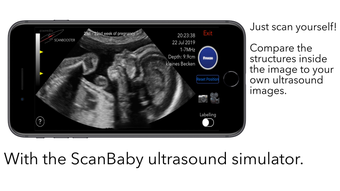

The app is divided into three different modes: Scan, Learn, and Watch. In Scan mode, users can scan a baby with labelling mode turned on to see all the important structures colored. This helps expecting parents understand the shown structures better and compare the ScanBaby image to their own ultrasound image. In Learn mode, users are taught about the developmental stages of their child through artfully crafted 3D scans of real babies that can be moved around. The scans come with labelling as well. Finally, in Watch mode, the app includes many different ultrasound videos that users might see during their own examination, with a short explanation of what can be seen.